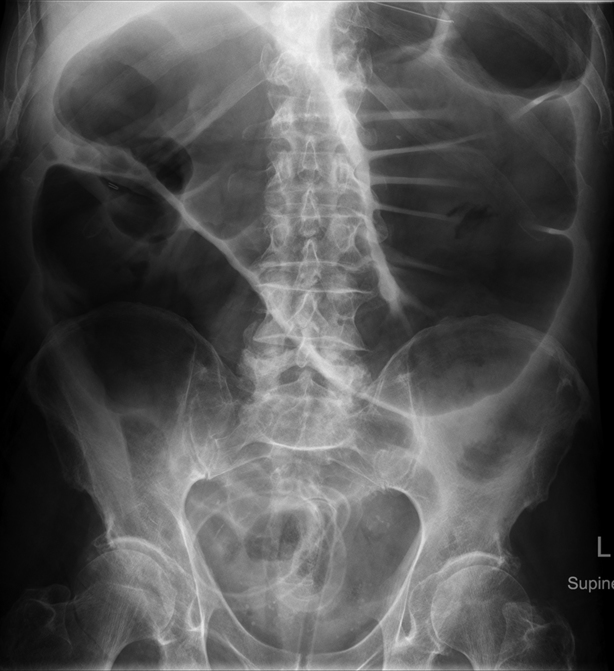

Dx

Dilated large colon (peripherally located and haustra don’t go wall to wall) proximally

-large bowel obstruction